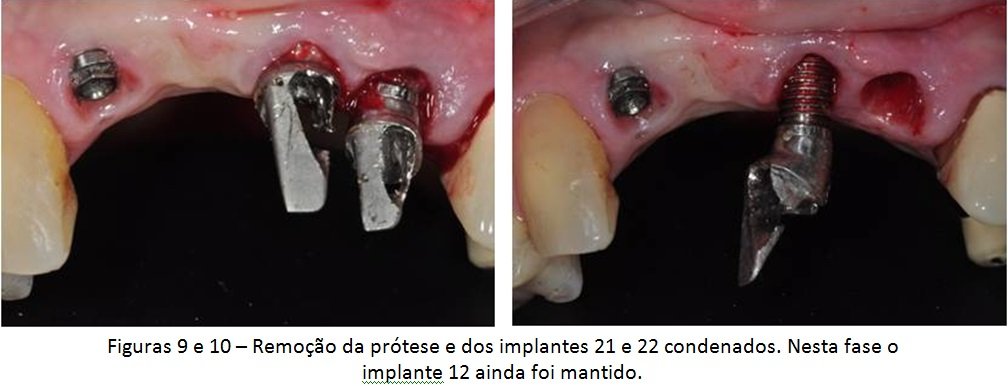

A paciente em questão foi diagnosticada com peri-implantite e recebeu tratamento cirúrgico para eliminação dos sinais e sintomas dessas alterações, mas a doença recorreu e ela acabou perdendo os implantes. A solução escolhida por nós foi o levantamento da cavidade nasal para possibilitar a colocação de dois novos implantes, viabilizando uma futura prótese fixa de quatro elementos. Veja a descrição detalhada do caso abaixo.